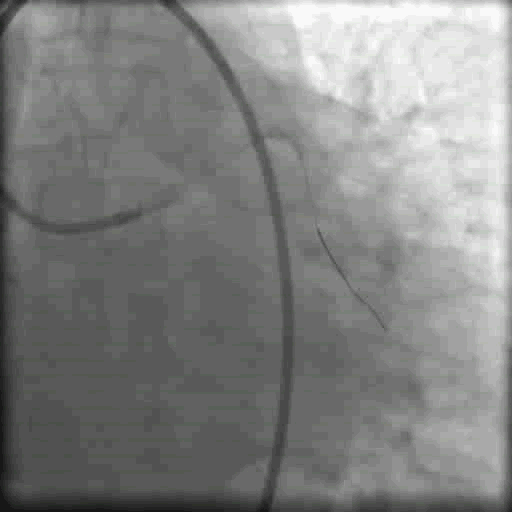

调整指引导丝GAIA2至LAD远端,对侧造影在真腔

李妍教授点评:

在CTO介入中应当时刻注意操作细节。右图GAIA 2 导丝头端已经形成knuckle,非常容易导致LAD远端穿孔,应当引起重视,开通闭塞血管后,应注意硬导丝远端走形,及时更换为软导丝再行支架植入。